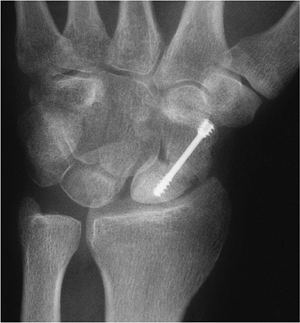

Fractures/Dislocations: Scaphoid Fractures

-

The scaphoid is the most commonly

fractured carpal bone in adults, accounting for 70% of all carpal

injuries. Scaphoid fractures in children account for only 2.9% of hand

and wrist fractures. -

Mechanism of injury: fall on the outstretched hand.

Scaphoid fractures may be difficult to detect and treat. Nonunion and avascular necrosis (AVN) are common complications.

Scaphoid fractures are classified by

fracture location and orientation of the fracture line. Fractures may

involve the (1) tubercle, (2) distal articular surface, (3) fracture of

the distal third, (4) waist fracture, or (5) proximal pole fracture (Fig. 9-12). -

Imaging of scaphoid fractures requires

AP, lateral, and scaphoid views. Displacement or obliteration of the

navicular fat stripe is a useful sign for subtle fractures.

Radionuclide scans, MRI, or CT may be useful for detecting subtle

fractures and evaluating complications. -

Treatment: cast immobilization for

undisplaced fractures. Displaced fractures (>1 mm step-off or

angulation) are treated with internal fixation. -

Complications: delayed union (failure to

unite in 3 months), nonunion, malunion, AVN (most common with proximal

pole fractures), radioscaphoid impingement, and arthrosis.

![]() |

FIGURE 9-16 PA view of a displaced scaphoid fracture with Herbert screw fixation. The proximal pole is sclerotic because of AVN.